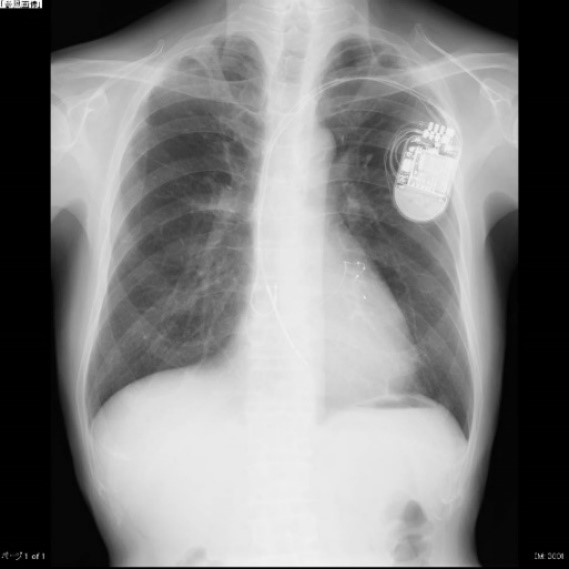

両心室ペーシング機能付き植込型除細動器移植術

(X線撮影)